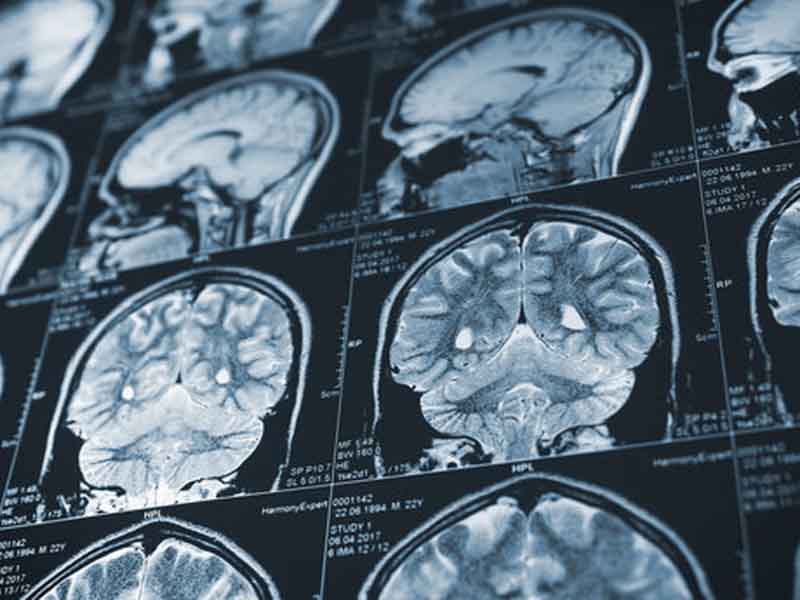

A CT scan, short for computed tomography scan, is a sophisticated imaging test that combines X-rays and computer technology to create detailed, cross-sectional images of your body.

Unlike a regular X-ray, which gives a flat image, a CT scan shows a more detailed, 3D view of your organs, bones, blood vessels, and tissues. This allows doctors to see inside your body with precision, making it easier to detect and diagnose various medical conditions.